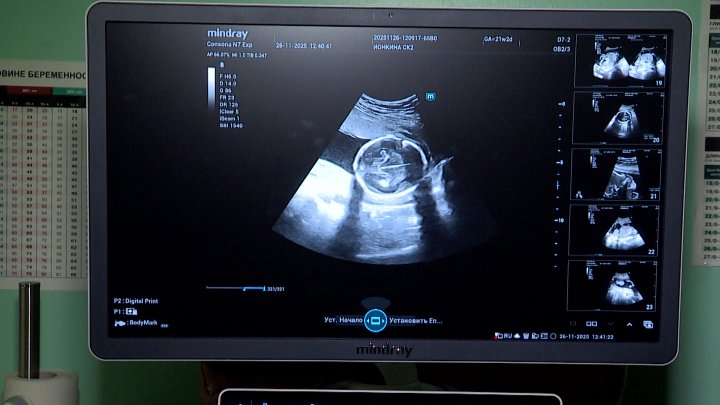

Долгожданный звук сердцебиения маленького чуда ждет с трепетом и нетерпением будущая мама. Такие плановые обследование проходя каждые три месяца беременности. Первый скрининг на 12–13 неделе для проверки правильного развития и исключения рисков. Второй — на 19–21 неделе, когда специалисты оценивают работу органов и исключают пороки. Третий скрининг на 30–34 неделе оценивает рост, положение, работу плаценты и количество вод, готовя маму к родам.

Мария САЛЬНИКОВА, врач ультразвуковой диагностики КБ№42 ФМБА России: «Ультразвуковое исследование в акушерстве обязательно на экспертном аппарате, который мы и получили. Четче стала картинка, в старом аппарате у нас шалило цветовое доплеровское картирование, теперь нам проще стало оценивать кровоток».

Благодаря новому аппарату УЗИ все записи на экране сохраняются в файлы, что упрощает работу врача. Но самым приятным на приеме становится ультразвуковая живопись, так ее называют специалисты, теперь будущая мама может увидеть своего малыша до рождения и понять, на кого он похож больше. В отделении ультразвуковой диагностики в акушерстве и гинекологии трудятся всего два специалиста — Мария Сальникова и Виктория Колесова. Ежегодно они проводят более двух тысяч исследований для будущих мам, помогая наблюдать, как развивается новая жизнь.

Мария САЛЬНИКОВА, врач ультразвуковой диагностики КБ№42 ФМБА России: «С аппаратом Mindray Consona N7 экспертного класса, конечно, более точное исследование проводится, более четкая картинка стала и проводит все расчеты, которые нужны нам именно в акушерстве. Потихоньку мы его осваиваем, пока очень нам тяжело, но все идет, с каждым днем все лучше и лучше, я думаю, что прогресс будет».